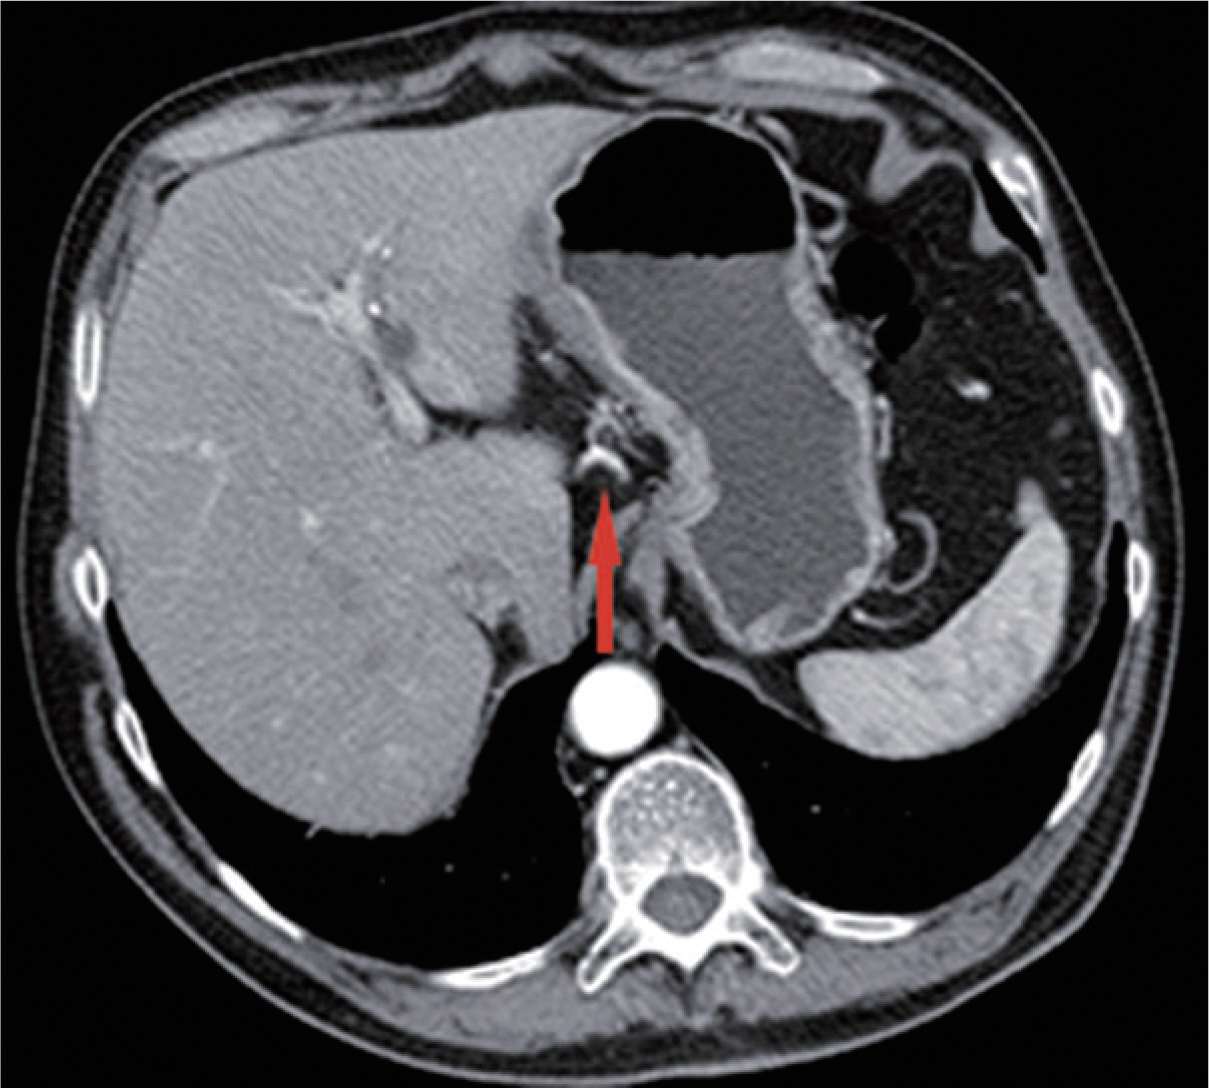

图2-36 结扎胃左动脉、静脉时,需小心可能存在的发自胃左动脉的副肝左动脉,这种变异的肝左动脉出现率为11.5%。术前CT扫描动脉成像可清楚显示变异的肝左动脉(红色箭头)。

图2-37 变异的肝左动脉(红色箭头)进入肝左叶。

图2-38 变异的肝左动脉。

图2-39 当变异的肝左动脉直径较粗时,应予以保留,以免肝左叶缺血,肝功能受损。可在发出副肝左动脉之后,结扎切断胃左动脉。